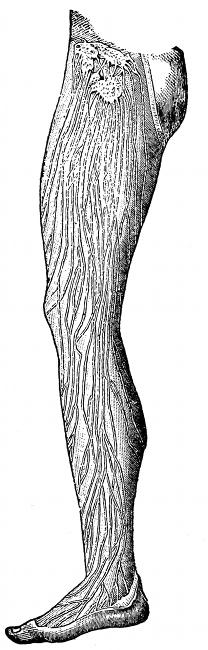

Fig. 4—Lymphatics of

the leg.

The other duct is called the

right lymphatic duct and receives

lymph from the upper part of

the right side of the thoracic wall,

part of the right side of the diaphragm

and the right lobe of the

liver, the whole of the right arm

and neck and right side of the

head. This trunk is very short

and empties its supply of lymph

into the right subclavian vein.